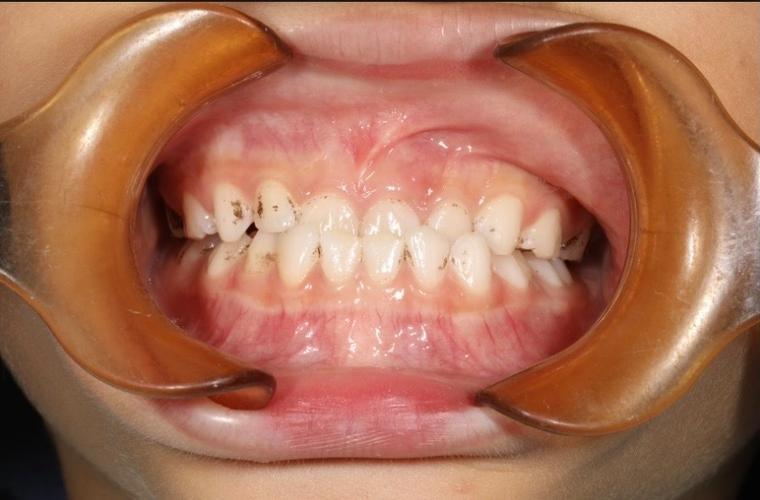

六、案例分享

8岁的乐乐,因长期口呼吸导致上牙弓狭窄。在楼凤网 人民医院,我们邀请耳鼻喉科会诊,帮助乐乐改善口呼吸问题后,为他佩戴扩弓器。经过6个月的治疗,不仅解决了牙弓狭窄的问题,口呼吸问题也一并得到了解决。看到乐乐自信的笑容,家长也松了一口气。